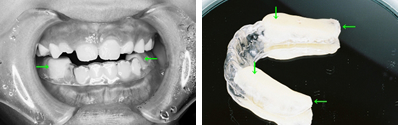

取り外しのできる簡単な装置で治療した例

各種検査で確認をした後に、上顎前歯を外に出すことが適当と判断された症例です。本人の性格やご家族の方の希望も考慮して治療方針が決定されます。取り外しのできる簡単な装置を用いて治療を開始しました。